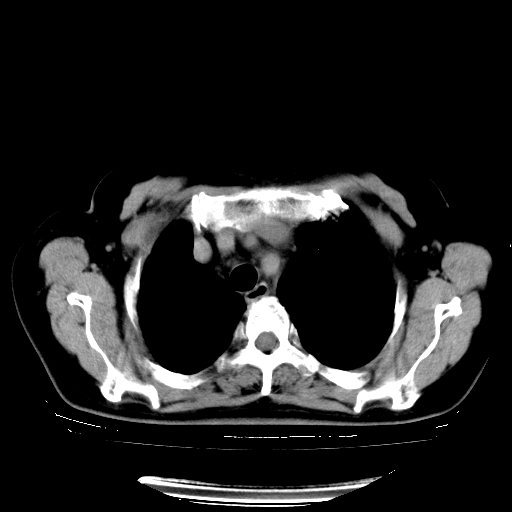

以下是引用zhangzhongshou在2008-3-22 12:52:00的发言:[br]1、右侧液气胸。[br]2、腹水。建议进一步检查。

以下是引用鲁巨ct在2008-3-22 14:10:00的发言:[br]1、右侧液气胸,右中下叶节段性不张。[br]2、腹水,建议上腹部ct检查

以下是引用zjzjr在2008-3-22 17:19:00的发言:[br]1、右侧液气胸,右下叶节段性不张。[br]2、腹水,建议上腹部ct检查